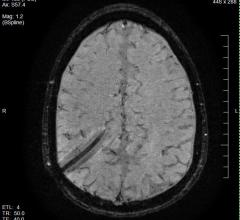

Today, perfusion MRI is primarily applied when diagnosing strokes and tumors. It measures which brain areas receive insufficient blood supply after a stroke occurs. It can also assess the viability and functionality of the liver and kidneys. Furthermore, the method can visualize which regions of a tumor are supplied with the most blood. In these areas, the ulcer grows the fastest, but is also more receptive to therapeutic treatment – helpful information for radiation therapists.

To perform perfusion MRI, physicians usually administer a contrast agent, which flows through the vessels with the blood and can be seen on the MR images due to its contrast. Among other things, the method can prove if a blood vessel in the brain has become porous due to a disease. In such cases, the contrast agent molecules can slip through the pores. The workshop was designed to bring the participants – primarily physicists, engineers, computer scientists and physicians – up to date and give them a foundation to further develop and apply the techniques in the clinical workflow.